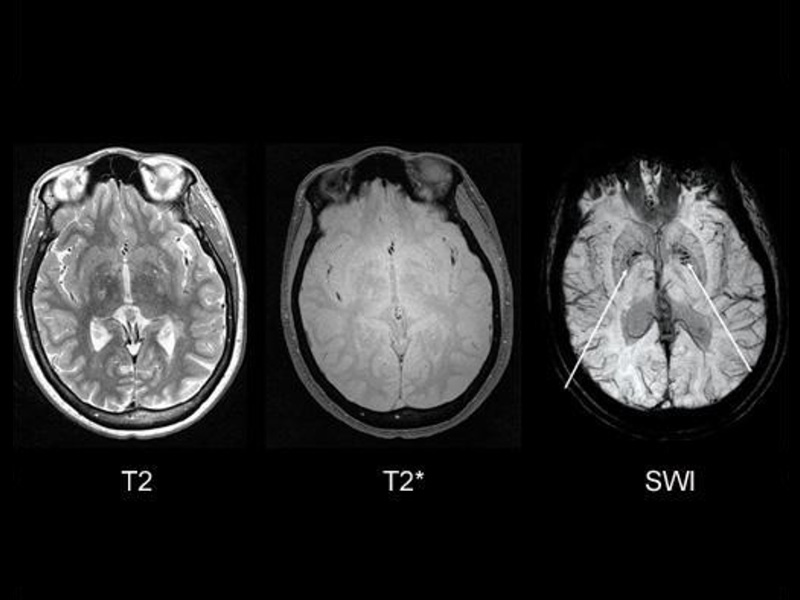

Gestational and Fetal MRI Technique Development and Clinical Applications

Our lab develops MRI techniques for non-invasive imaging of fetal and maternal physiology during pregnancy. These methods enhance our ability to investigate tissue metabolism, microstructure, and function, with applications in maternal screening and early detection of gestational complications. By employing approaches such as Saturation Transfer (ST) imaging, relaxometry, and Susceptibility-Weighted Imaging (SWI), our MRI techniques are sensitive to changes in tissue function that cannot be imaged with conventional clinical MRI. With these techniques, we aim to extend the capabilities of MRI in ways that support accessibility and clinical translation.